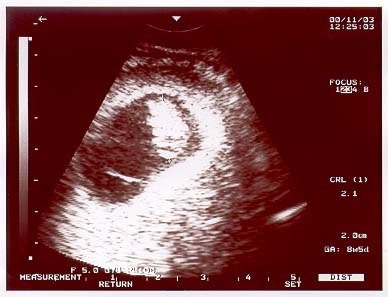

These images show the baby at 17wks. (Dec. 29, 2000) |

Image sequence 1 of 3 |